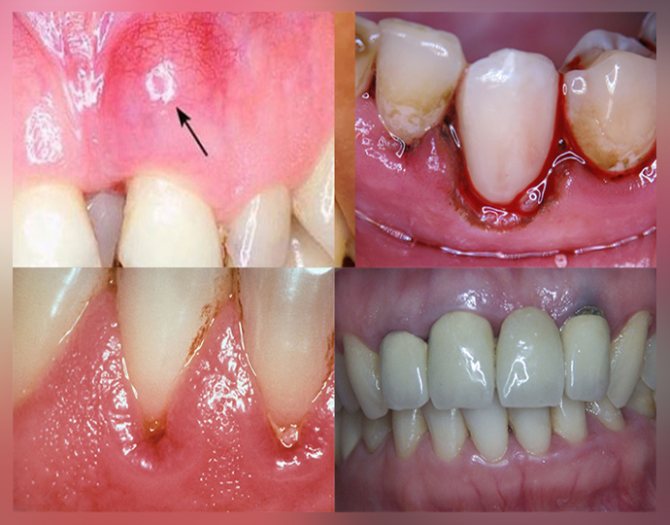

Симптомы (первые признаки и последующие, фото)

- Изменения цвета десны. Пигментация пораженных участков мягких тканей возникает вследствие нарушения их структуры. В результате клетки насыщаются пигментом. Злокачественный процесс в этом случае несложно распознать по багровым областям челюсти, эрозиям и белым фрагментам очагового типа.

- Специфическая окраска. Опухолевые клетки расположены хаотично. Они имеют особое свойство накапливать пигмент. В результате на десне возникает окрашенный участок. Он может быть белёсым, багровым или ярко-красным. Это важный диагностический признак ракового процесса.

- Возникновение небольших кровоточивых эрозий на уплотненной слизистой десны. Видна ее белесоватая пигментация. Возможны болевые ощущения.

Симптомы начальной стадии, первые признаки, фото

- изменение вида самой слизистой оболочки десны, позволяющее отличить рак от доброкачественного палилломатоза или свища: появление красных прожилок, точек, бугорков с дефектами ткани – эрозиями, язвочками с четко очерченными краями;

- начальная стадия рака десны характеризуется расположением опухолевого образования на нижней челюсти возле передней группы зубов в виде шишковидных наростов размером до 1 см, края их сглажены, без четких границ и формы;

Виды и классификация

Как выглядит рак десен? На первом этапе развития может появиться незначительная припухлость, покрытая слизистой оболочкой, и очень мягкая на ощупь. В некоторых случаях начальная стадия рака десен характеризуется появлением небольших эрозий или белесых бляшек, которые сливаются между собой, образуя большой очаг поражения.

Злокачественная опухоль подразделяется на три формы, в зависимости от того, как выглядит рак десен:

- Язвенная – выглядит как изъявление слизистой оболочки, имеющее неровные края, кровоточащее при прикосновении.

- Папилломатозная (сосочковая) – представляет собой бугорок с неровными краями, внешне может выглядеть, как головка цветной капусты.

- Инфильтративная – глубокое поражение, не имеющее четких границ.